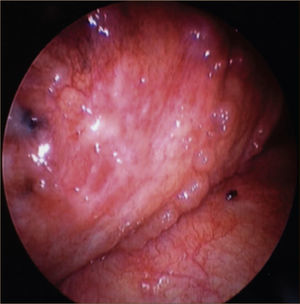

La toracoscopía médica puede ser realizada en sala de endoscopía o en pabellón, con anestesia local y sedación e.v. No requiere intubación. Se accede a la cavidad pleural por un portal de entrada de 10mm, no requiere de estadía en sala de postoperados en forma obligada. Se drena en forma segura todo el derrame contenido en la cavidad pleural y luego se inspecciona la cavidad. Permite tomar biopsias grandes bajo visión directa sobre la pleura parietal, pulmón y diafragma que permitirán hacer estudios moleculares y de inmunohistoquímica al tejido y además permite efectuar pleurodesis en el mismo procedimiento44. (Figuras 5–7).